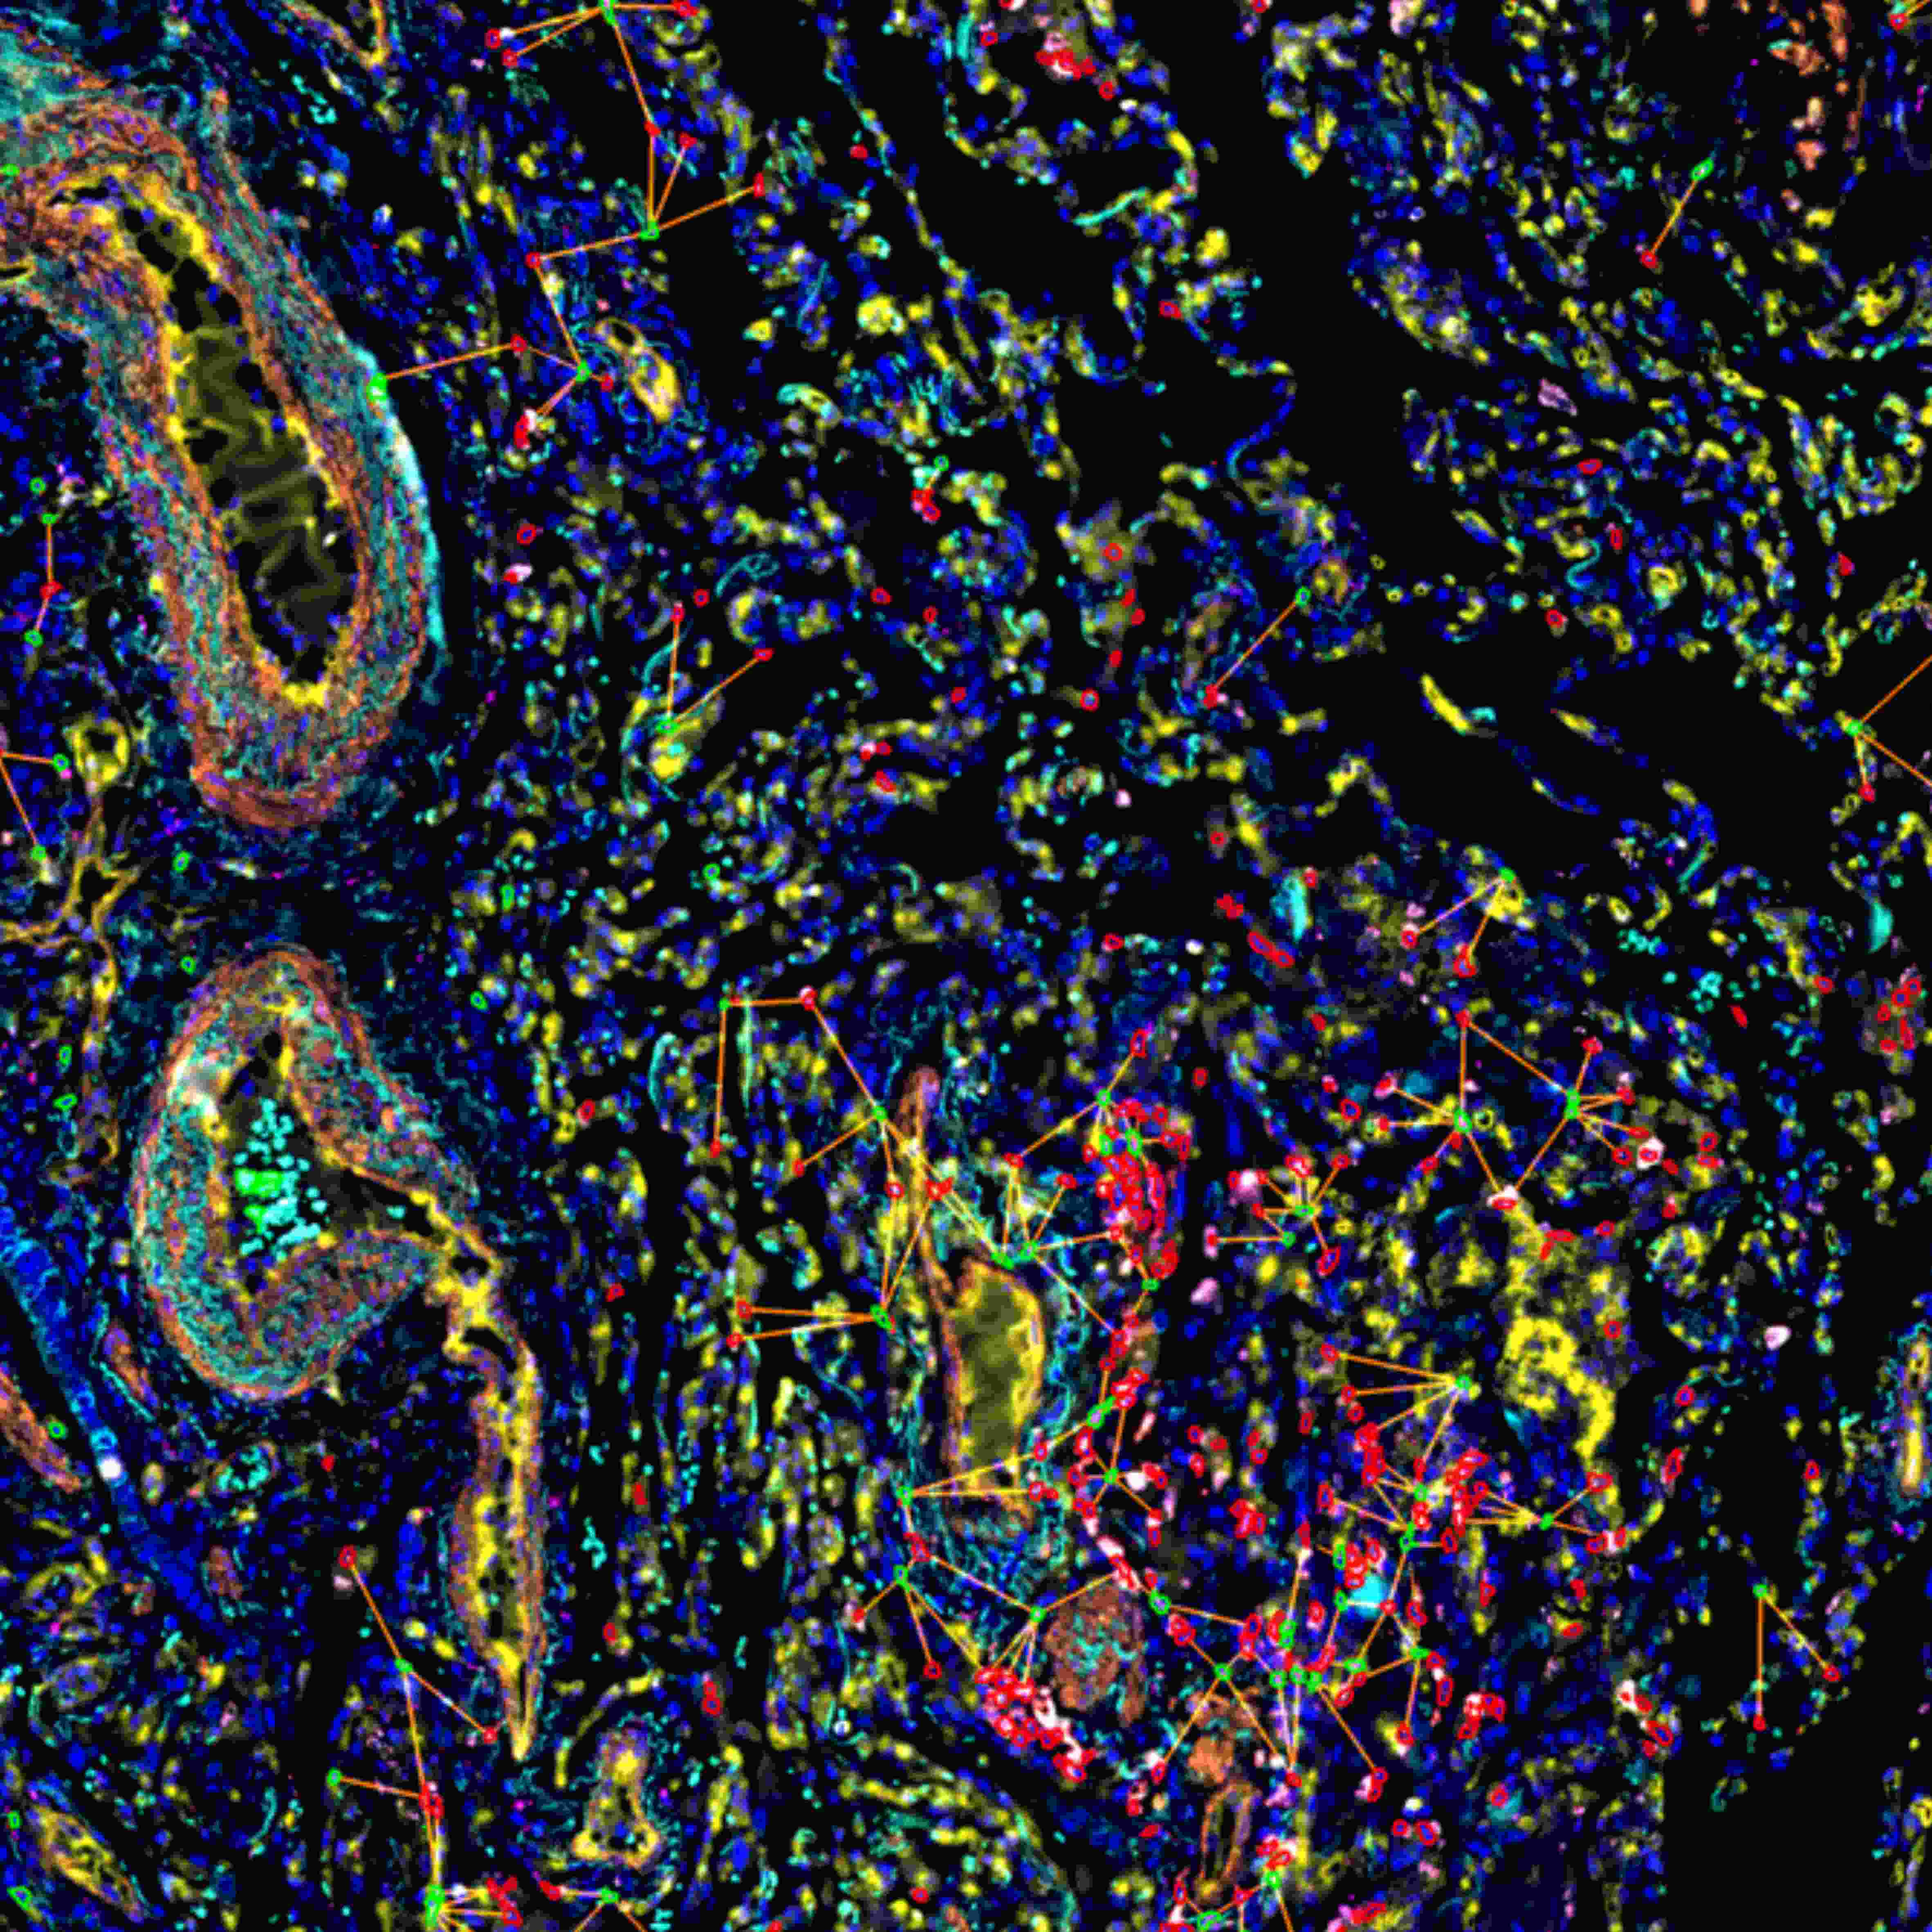

在单细胞表型分析与组织识别分析的基础上,利用StrataQuest可进一步分析不同细胞与不同组织类型间的空间分析关系。

除上述一站式完整解决方案外,TissueGnostics 还能助力研究人员开展更深入的实验方法研究,通过定制化染色扫描分析服务获取更丰富的分析数据。例如,在组织切片染色扫描环节,可依据实验方案实现 50 种以上荧光标记的多轮循环染色扫描;后续分析中,还能生成空间水平的细胞间连线图、组织周围特定距离细胞分布图等多元化结果。